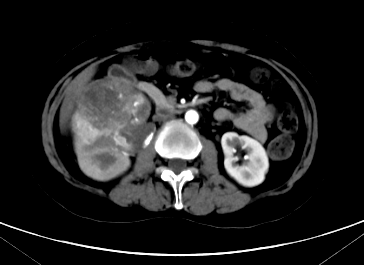

腹部CT平扫

腹部CT增强扫描

泌尿外科林伟广副主任医师接诊后,为宗女士进行详细的B超检查,结果报告提示“右肾下极不均密度占位改变”,初步考虑右肾肿瘤,随后安排进一步检查,最后发现宗女士的肿瘤位于右肾中、下极,大小竟然有9厘米,足有一个苹果般大小。